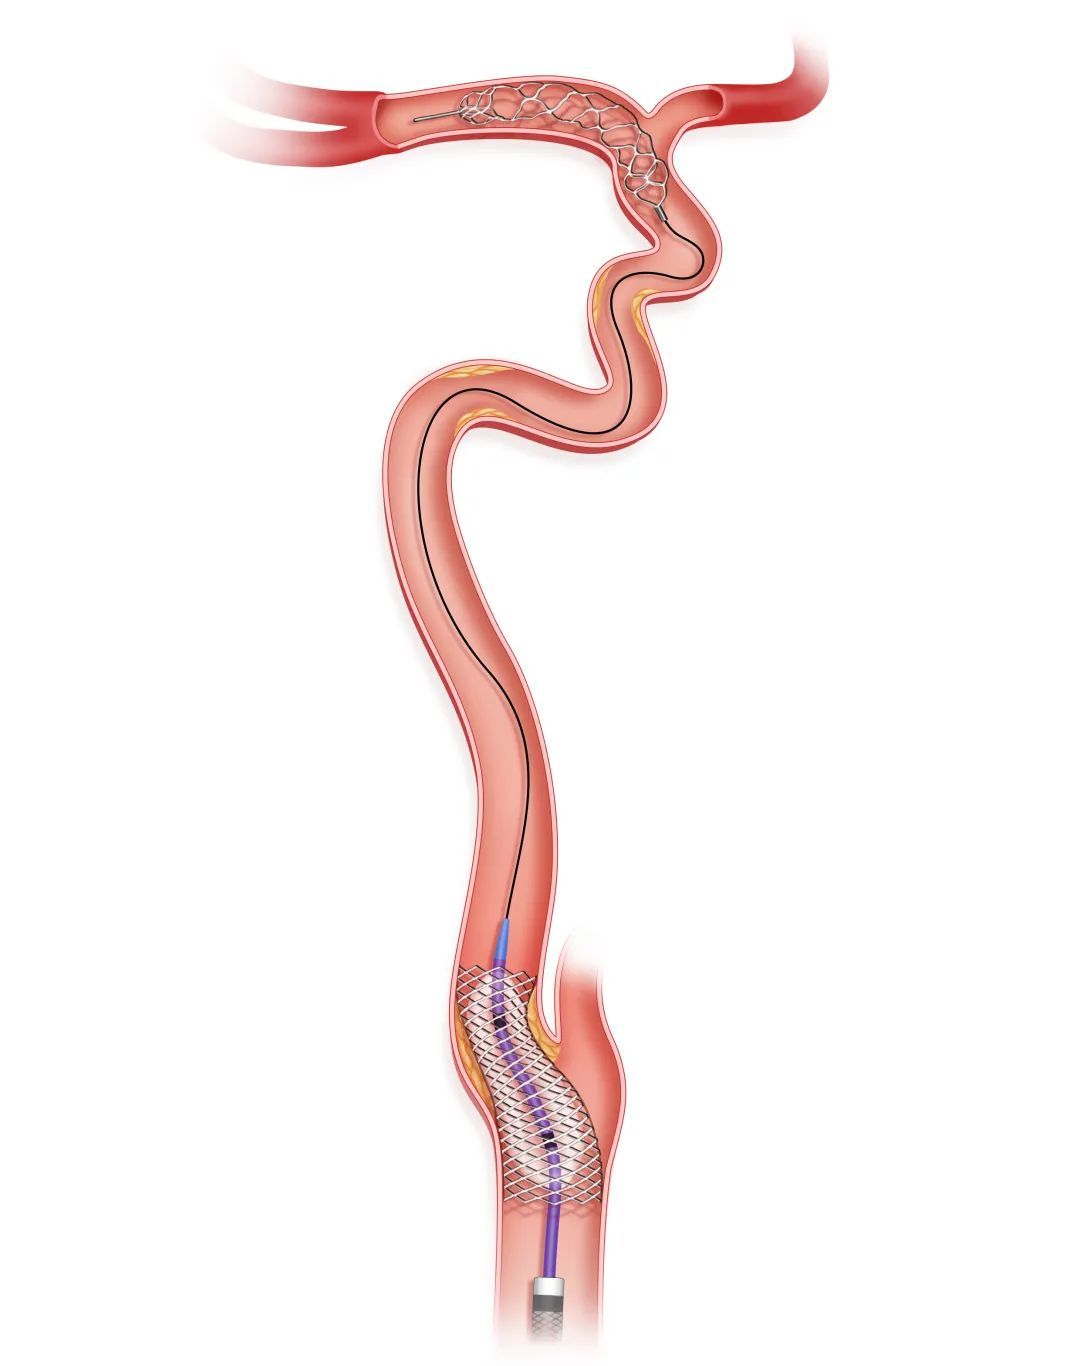

步骤五

球囊和/或支架血管成形

再次释放Syphonet®取栓支架,选取合适的SacSpeed®球囊扩张导管扩张残余的严重狭窄部位。应尽量避免支架置入,在出现明显限流性夹层、斑块回缩明显限制前向血流的部位,可考虑经Syphonet®取栓支架输送导丝送入支架系统,支架释放后进行球囊后扩张以提高支架贴壁性,降低再狭窄和再闭塞率。